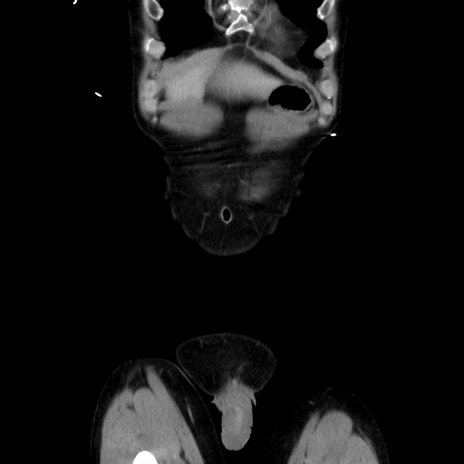

症例37(冠状断像)

横断像